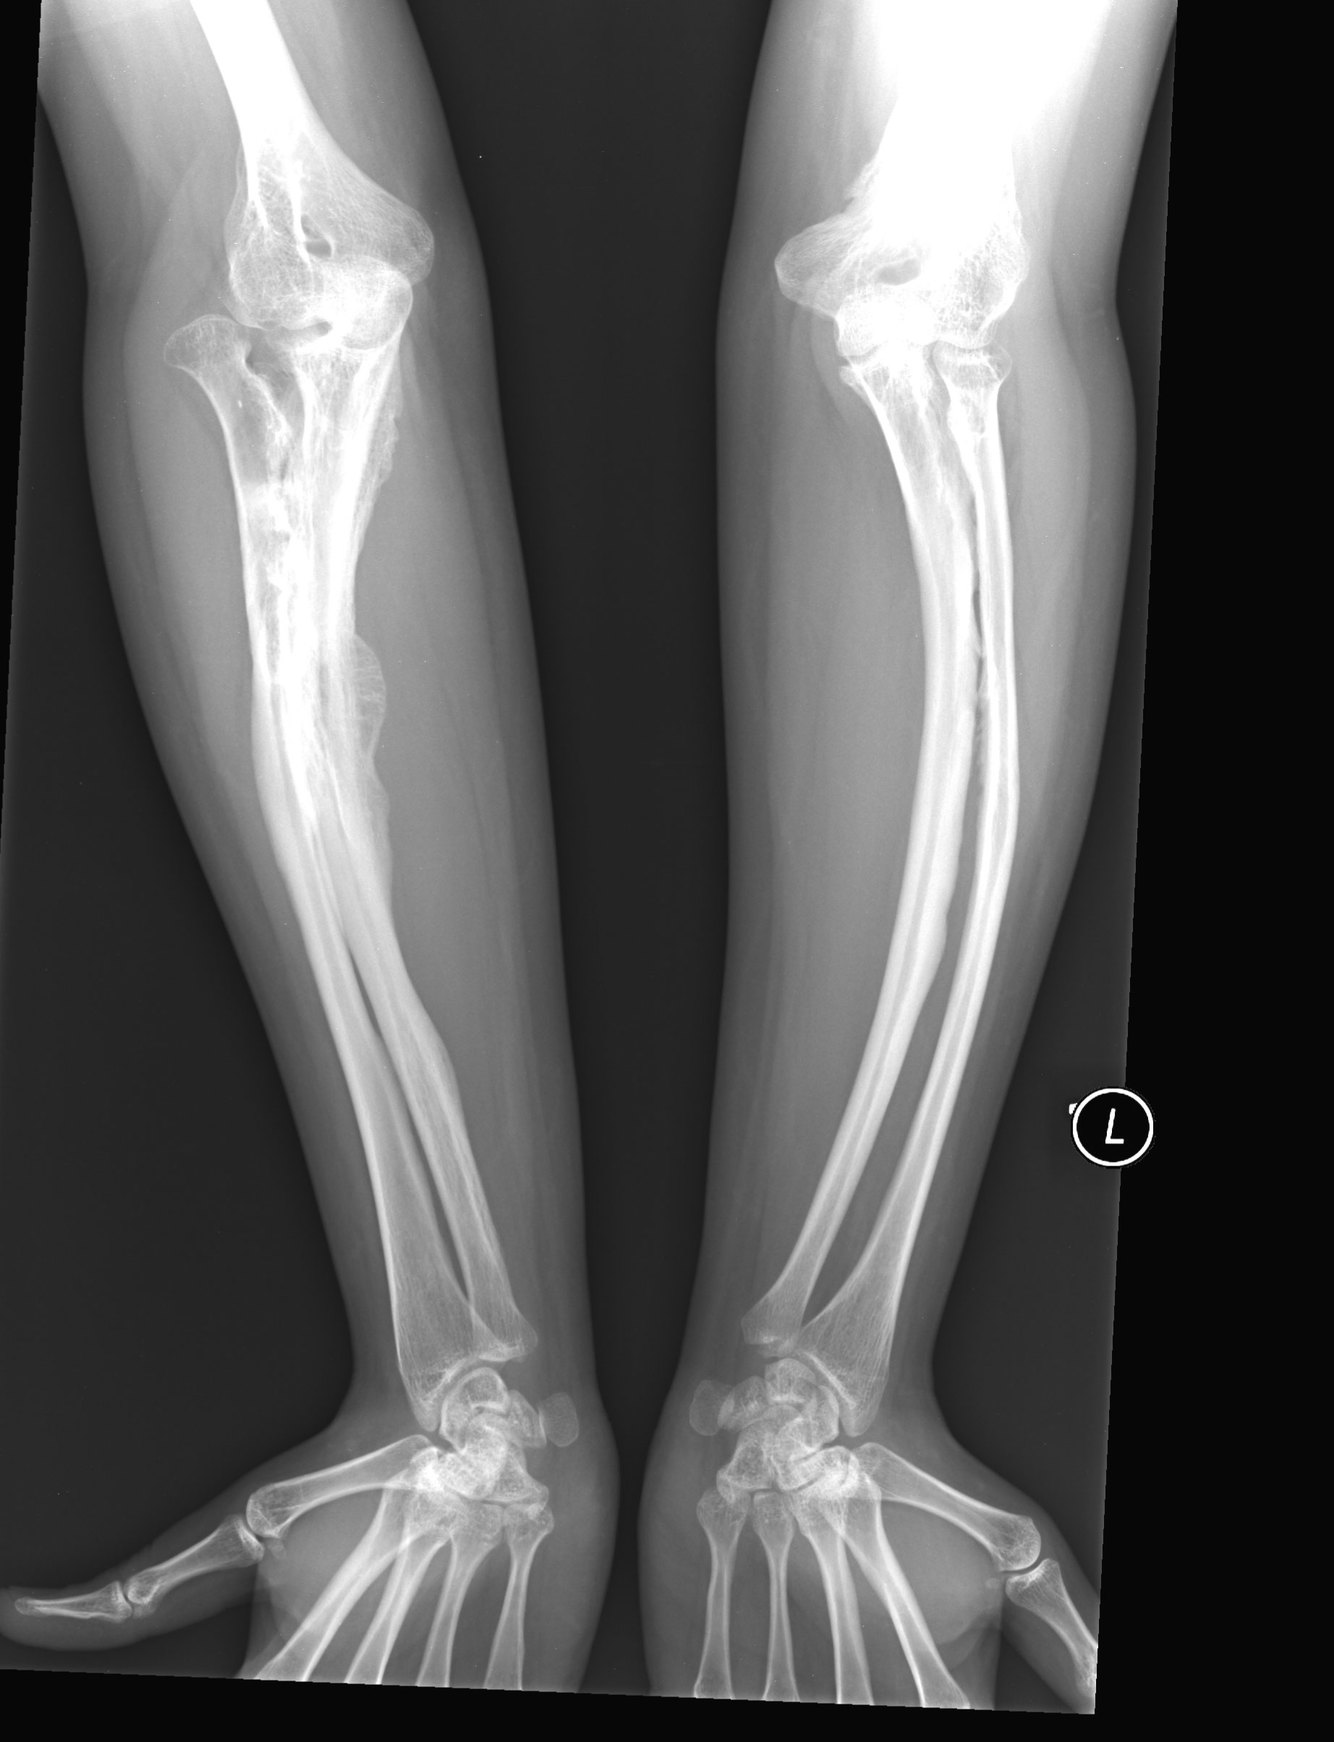

Xrays: Osteopenia (low bone density), Bowing, Wormian bone of skull

Xray features of osteogenesis imperfecta

Osteopenia (low bone density)

Bowing

Wormian bones in the skull

( Bowing of bones – another symtom)